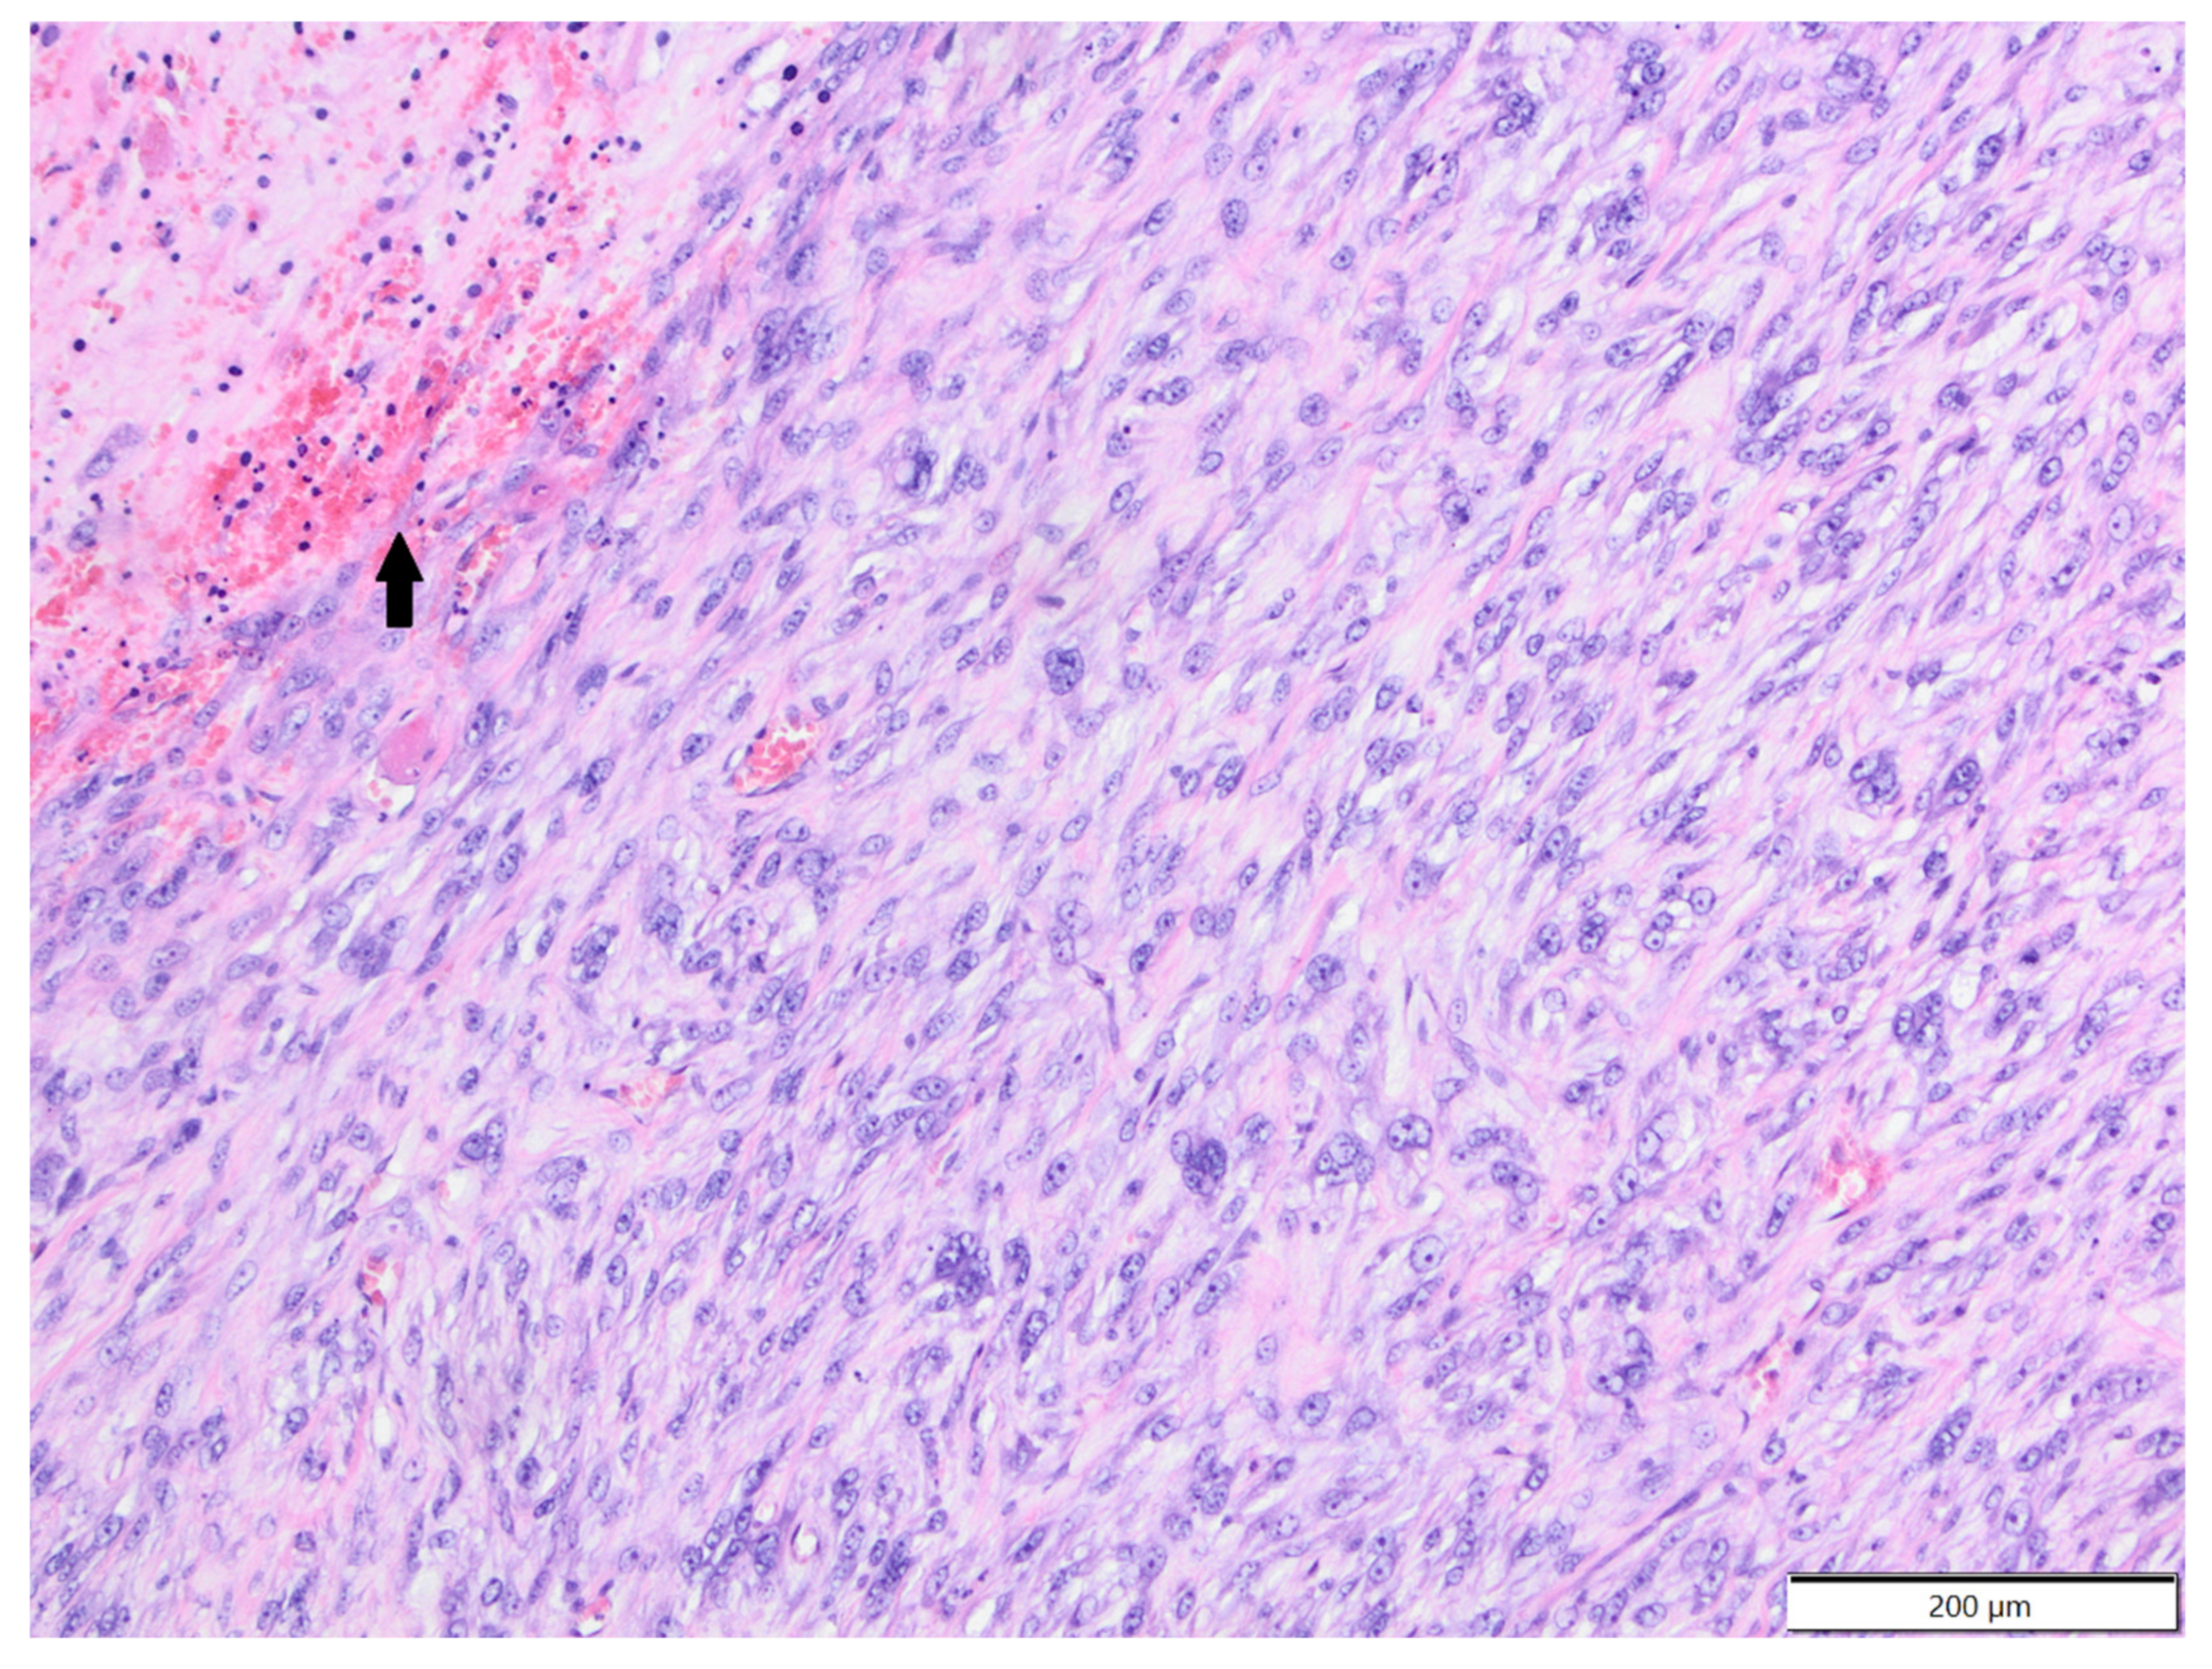

3.2. Rats

| 2 | Histiocytic sarcoma | 3.8% | 1 | 1 | 20 months |